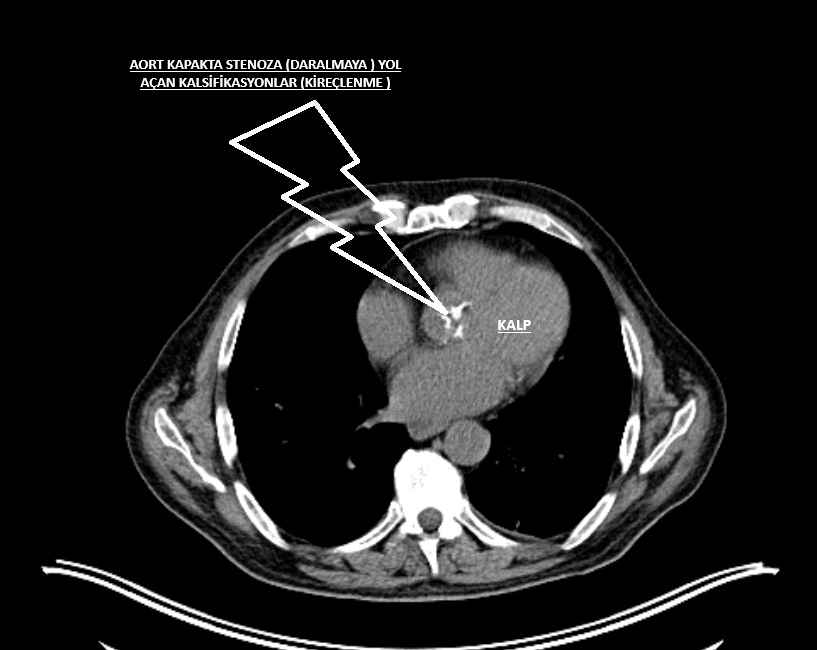

Resim 1: Göğüs Tomografisinde görülen aort kapaktaki kireçlenme (kalsifikasyon)